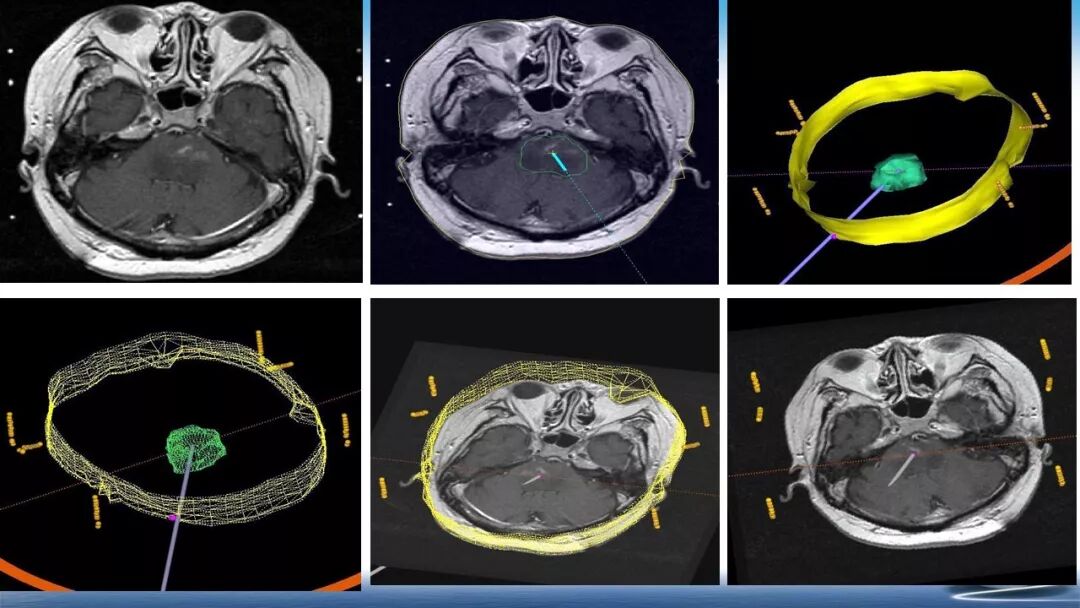

立体定向活检在脑干中线病变精准诊断中的作用

今天为大家带来的是中国人民解放军总医院第六医学中心(原中国人民解放军海军总医院)王亚明、于新、张剑宁带来的精彩课题分享:立体定向活检在脑干中线病变精准诊断中的作用,欢迎观看、阅读!